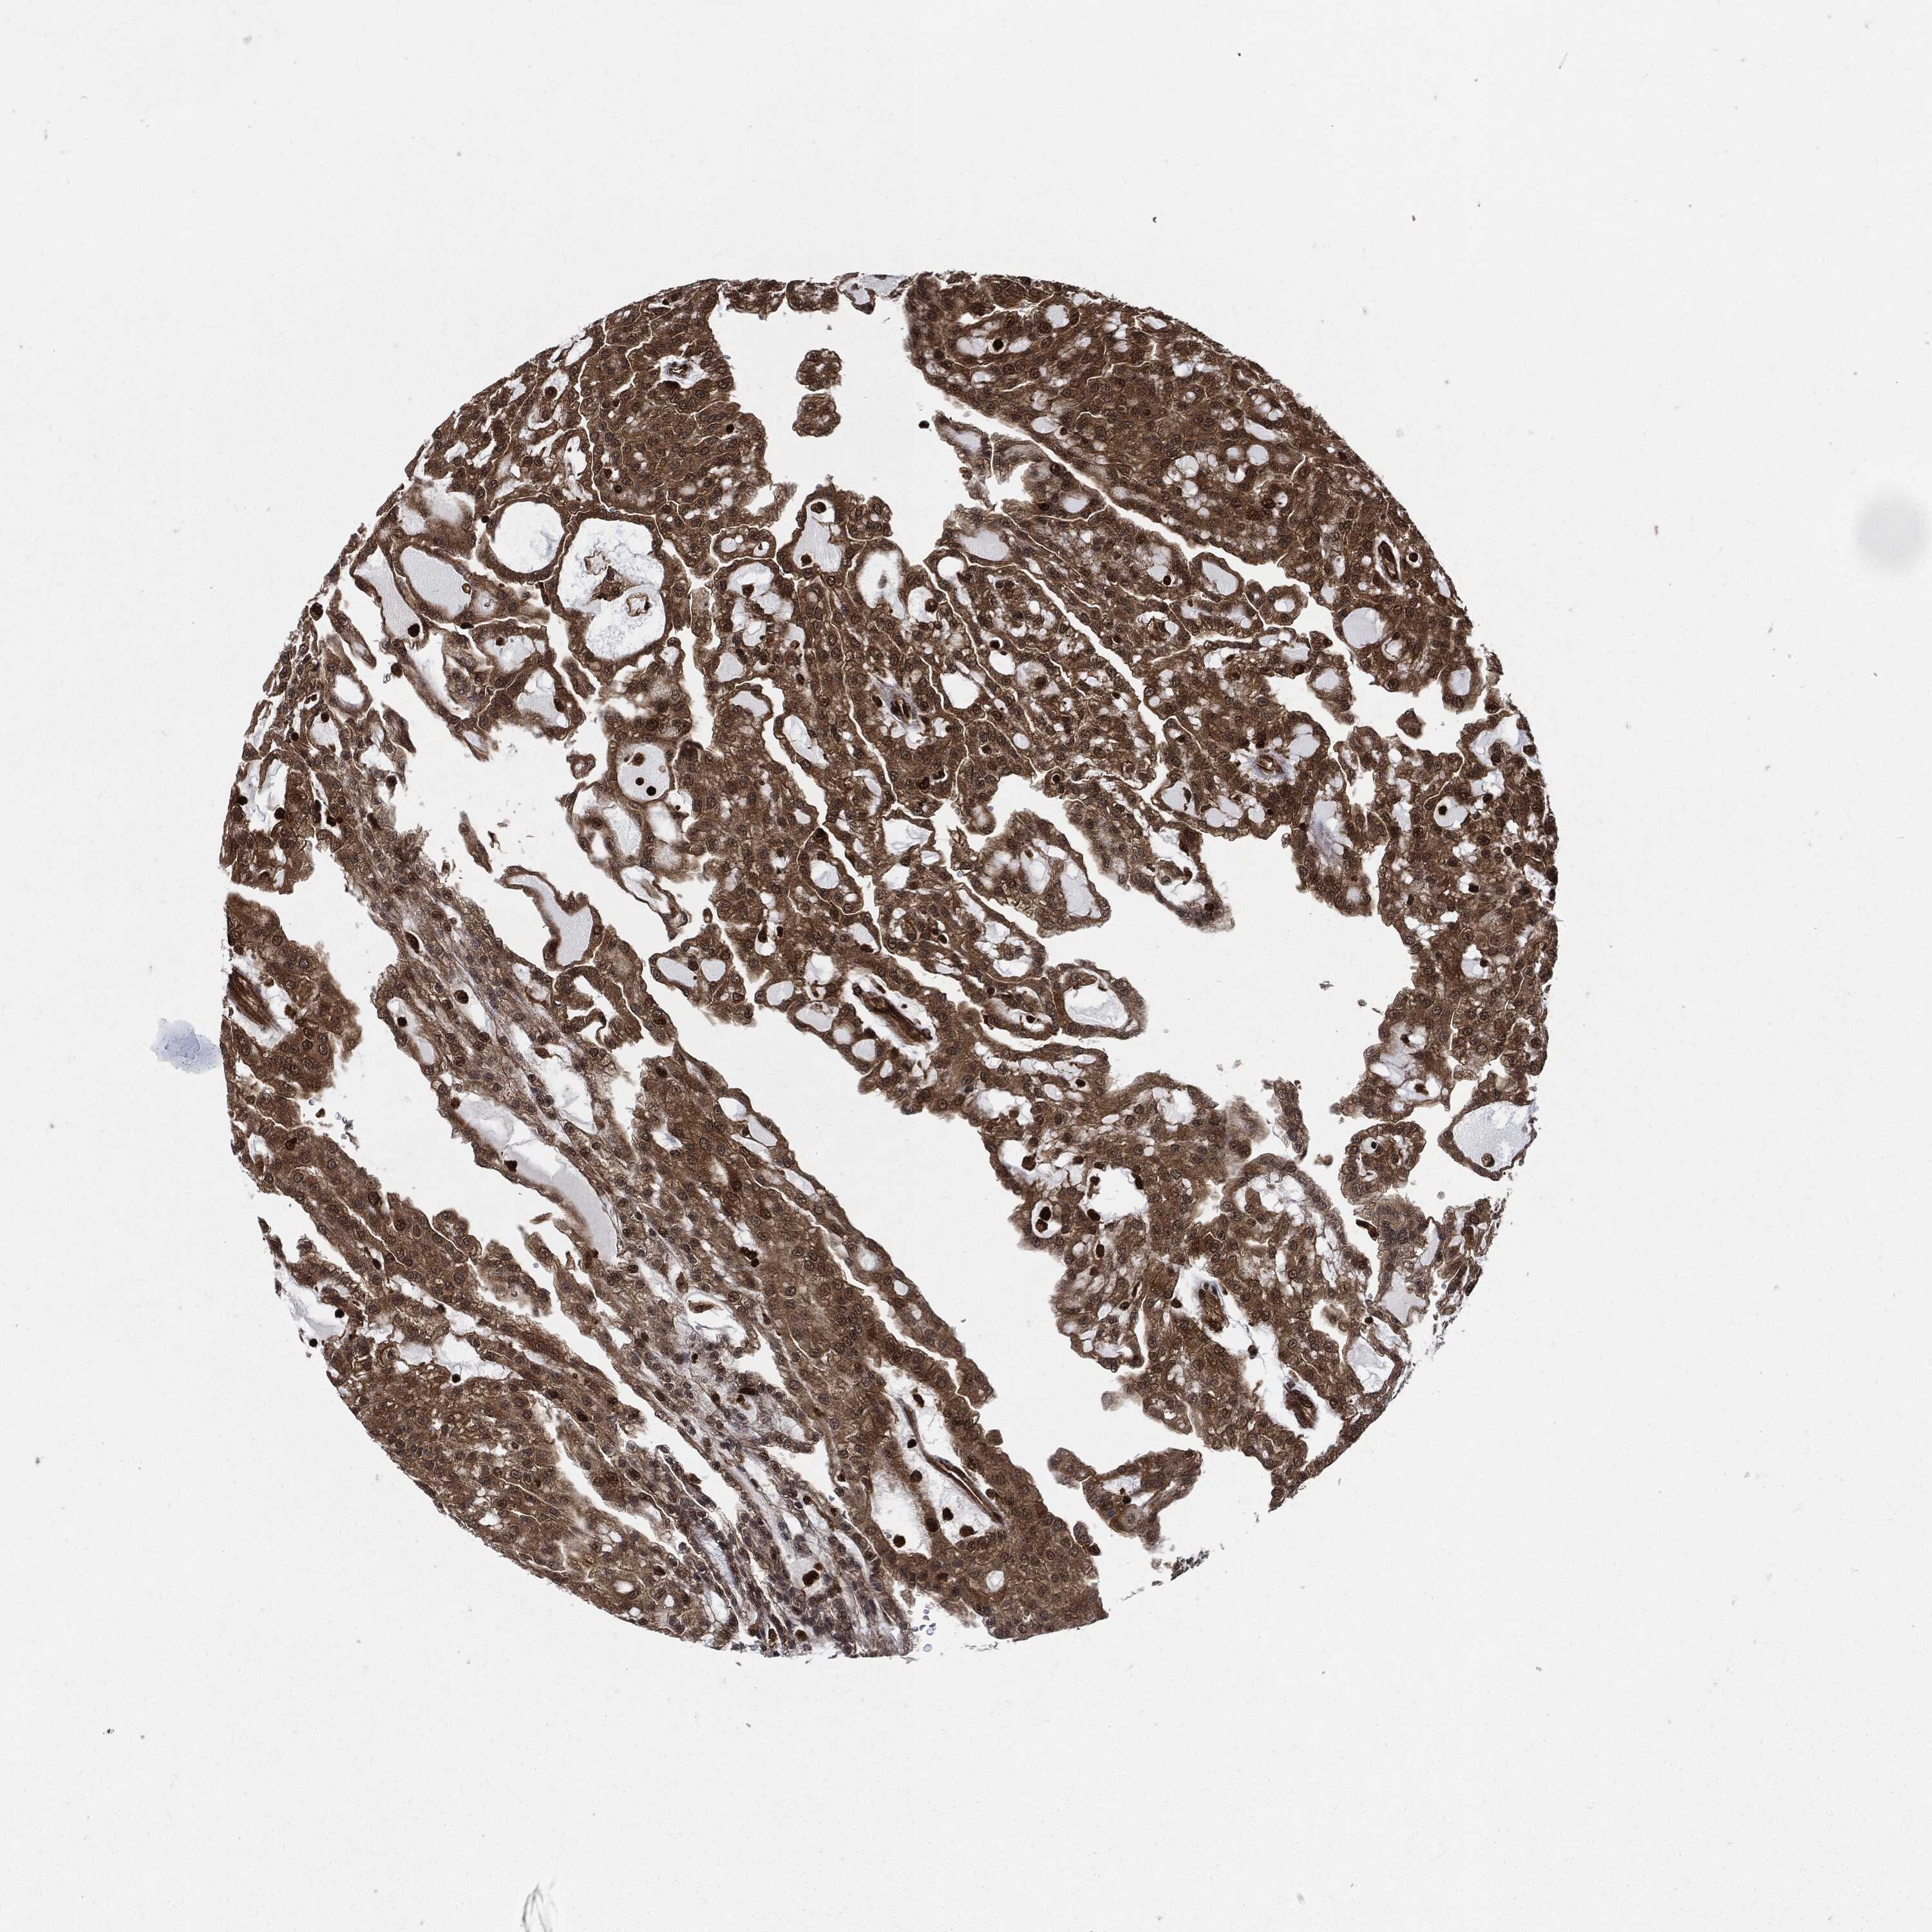

CANCER RENAL CANCER Show tissue menu

KICH TCGA KIRC TCGA KIRC VALIDATION KIRP TCGA PROTEIN RCC CPTAC PROTEIN EXPRESSION